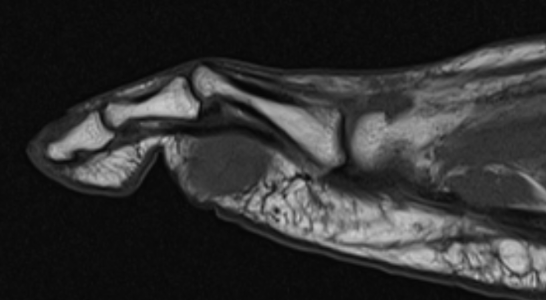

GCT flexor tendon sheath

GCT of tibialis posterior tendon sheath